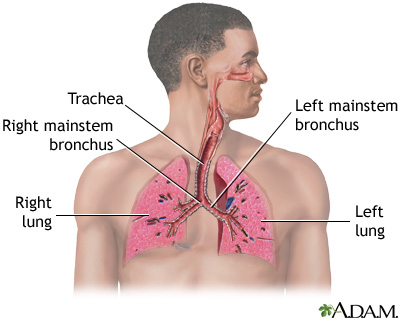

Sarcoidosis is a disease in which inflammation occurs in the lymph nodes, lungs, liver, eyes, skin, and other tissues.

The disease can affect almost any organ. It most commonly affects the lungs.